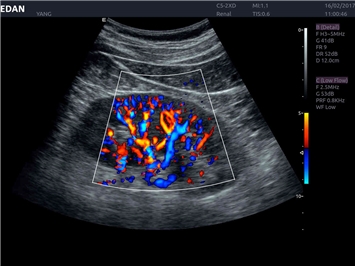

EDAN Acclarix LX4

Расширьте свои представления. Использование усовершенствованной платформой Acclarix система LX4 обеспечивает непревзойденную четкость изображений и интеллектуальный рабочий процесс для всех пользователей, являясь при этом наиболее экономичным решением.

EDAN Acclarix LX4 представляет собой инновационную ультразвуковую систему, построенную на усовершенствованной платформе Acclarix. Сочетание высокого качества визуализации с интеллектуальным рабочим процессом делает эту систему оптимальным выбором для клиник, ценящих эффективность и экономичность.

Трехмерная реконструкция ЦДК:

Да

Color 3D: